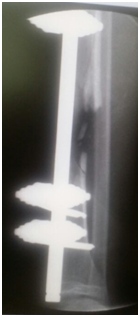

Nerve conduction study showed evidence of axonal motor nerve injury of the right peroneal nerve. In addition, the right tibial nerve also showed mild motor axonal injury. We decided to do Masqulete procedure, in association with our plastic team to do a muscle flap and nerve grafting. Careful debridement and irrigation with refreshment of the fracture ends were done. The defect filled with polymethylmethacrylate (PMMA) cement spacer rotation al flap and skin graft were performed at the same operation.

After seven weeks, second stage was performed. The bone was approached through an incision on the edge of the muscle flap, the membrane was well formed, it incised, the cement spacer removed and the space was filled with autograft and synthetic bone graft (Figure 4). Peroneal nerve was explored and tagged with aim to do nerve grafting after 3 months.

Figure 4 AP x-ray of the leg post removal of the cement spacer and filling the membrane with bone graft.

• Figure 3a & b Photo and tibial x-ray during the operation and insertion of the bone cement spacer after debridement of defect.